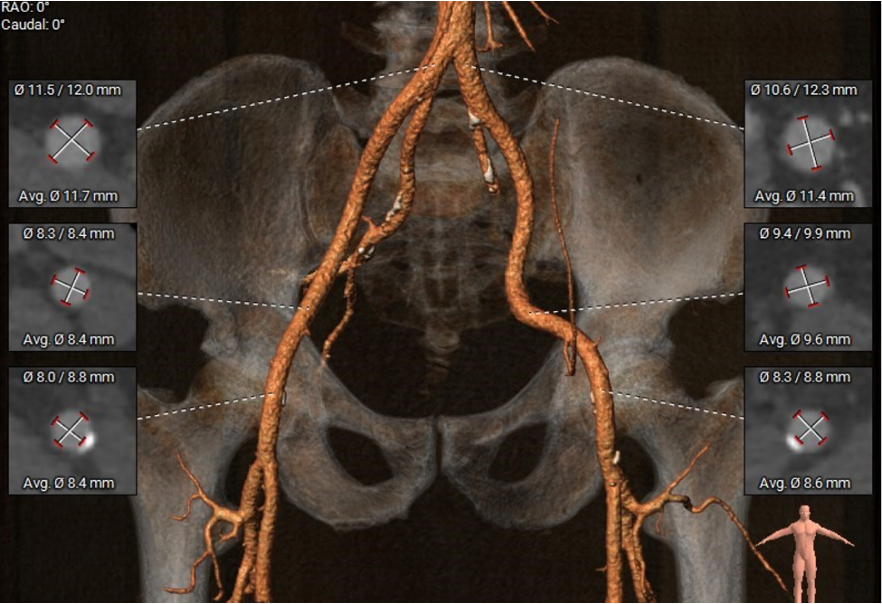

外周血管及主动脉弓解剖

手术过程概览